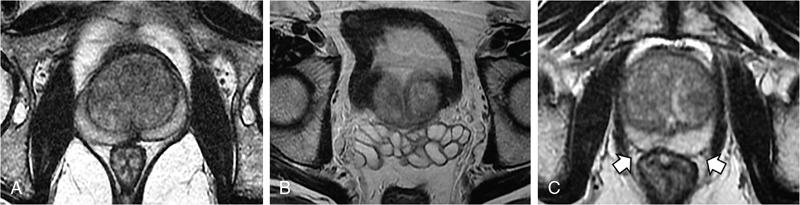

MULTIPARAMETRIC MRI OF THE PROSTRATE Dayala Sundaram Worldwide prostate cancer is the most common solid organ malignancy and the second most common cancer in men. The incidence of prostate cancer in India is 3.9 per 100,000 men and contributes 9% of all cancer-related mortality. Traditionally, serum prostate specific antigen (PSA) and digital rectal examination (DRE) are used as screening tools, and systematic transrectal ultrasound (TRUS)-guided biopsy is considered as the gold standard for confirmation for the detection of cancer prostate. Nevertheless, this combined approach has led to the risk of overdiagnosis and overtreatment of clinically insignificant low volume and indolent tumours. On the other hand, tumour in the anterior aspect of the gland tends to be missed by TRUS-guided biopsy until they grow to a substantial size and reach within 15–20 mm from the posterior margin, leading to delayed diagnosis. Moreover, systematic TRUS biopsy has also proven to underestimate the final Gleason score of the tumour following radical prostatectomy, leading to inaccurate triaging and selection of therapeutic options. Multiparametric magnetic resonance imaging (mpMRI) changed the paradigms on prostate cancer detection. It struck a balance between underdiagnosis and overdiagnosis with a clinical priority not to miss any clinically significant cancer (Gleason score ≥4 + 3, and/or volume ≥0.5 cc, and/or extraprostatic extension). Initially, MRI was not used for the primary detection of the tumour, but it was mainly used for locoregional staging in biopsy-proven patients since it provided only morphologic information with T1-weighted imaging (TIW) and T2-weighted imaging (T2WI). Ever since the introduction of mpMRI, which combines the morphological assessment of T2WI and molecular and physiologic assessment by diffusion-weighted imaging (DWI) and dynamic contrast-enhanced (DCE) imaging, it has been used in primary tumour detection as well as staging. Over the period, mpMRI has been proven to have high sensitivity and negative predictive value (NPV) in diagnosing clinically significant prostate cancer, however, with more variable specificity. A positive association has also been established between abnormal mpMRI and increased tumour volume and high grade. Overall, the introduction of mpMRI has changed the traditional diagnostic pathway in the management of prostate cancer (Fig. 11.24.1.1). Efforts were taken to improve the global standardization in image acquisition, interpretation and reporting of mpMRI of prostate and prostate imaging reporting and data system (PI-RADS) was introduced in 2012. T1WI, T2WI, DWI, DCE and spectroscopy were identified as the key sequences. In 2015, PI-RADS version 2 (v2) was released with the inclusion of key advancements in image acquisition and incorporation of a five-point final assessment scoring system for peripheral zone (PZ) and transition zone (TZ). Spectroscopy was excluded in PI-RADS v2. The recent update, PI-RADS version 2.1 (v2.1), proposed in 2019, endorses small adjustments to obviate ambiguities in the scoring system and reduces inter-reader variability. PI-RADS is intended for detection, localization and risk stratification in patients with suspected cancer in the prostate gland and staging the confirmed cases. However, detection of recurrence, progression during active surveillance and evaluation of other parts of the body (e.g. skeletal system) are not included in PI-RADS. In mpMRI following recent TRUS-guided biopsy, the postbiopsy haemorrhage in the prostate gland and seminal vesicles may confound assessment. Since the postbiopsy changes may persist for many months, and it may not always be feasible or necessary to postpone the MRI examination. Moreover, if mpMRI is performed following a negative TRUS biopsy, the possibility for clinically significant prostate cancer (csPCa) at the site of postbiopsy haemorrhage is less likely without corresponding suspicious finding on MRI. If postbiopsy haemorrhage or inflammation adversely affects the interpretation of a study, then at least 6 weeks or longer should be considered for follow-up. MR spectroscopy was recommended in PI-RADS v1. However, no incremental value was acclaimed by MR spectroscopy in routine clinical use despite prolonging the duration of the study and requirement of dedicated software. Hence, MR spectroscopy was not included in PI-RADS v2. High-resolution T2WI is the fundamental sequence in mpMRI useful to identify the zonal anatomy, assess abnormality within the gland, seminal vesicle invasion, extraprostatic extension and nodal metastasis. Due to high glandular content, the normal PZ appears as homogeneously hyperintense. Whereas, due to high cellularity and less water content, the clinically significant cancer in the PZ usually appears as a hypointense focus. Moreover, the decrease in intensity on T2WI is proven to be positively associated with the aggressiveness of the tumour. Due to the high cellularity, the normal TZ also appears heterogeneously hypointense, which makes the detection of cancer difficult in the TZ. Caveats: Benign conditions like prostatitis, haemorrhage, glandular hypertrophy, postbiopsy scar and post-therapy changes may show similar hypointensity. Benign stromal elements may appear hypointense in the TZ. Scoring: PI-RADS v2.1 recommends separate five-point scoring system for lesions in PZ and TZ based on T2WI. However, T2WI scoring is used only in overall risk assessment of TZ lesions and caries no significance in PZ lesions (Table 11.24.1.1). DWI quantifies the degree of the random movement of water molecules within the prostate. Due to high cellularity, the motion of the water molecules is inhibited within the tumour, which is seen as a high signal on DWI and low signal intensity on apparent diffusion coefficient (ADC) maps. It is recommended to obtain one low b-value image set at 50–100 s/mm2 and one intermediate b-value image set at 800–1000 s/mm2. b50 is used instead of b0 to prevent shine through of vessels. A high b-value image set with ≥1400 s/mm2 is also mandatory, which preferably should be acquired separately or calculated from low and intermediate b-value images. According to PI-RADS v2.1, high b-value image (≥1400 s/mm2) must be used for interpretation. In the high b-value image (≥1,400 s/mm2), background signal from the nonmalignant tissue is suppressed; hence, the sensitivity and accuracy are increased (Fig. 11.24.1.2). Moreover, the degree of signal reduction on ADC map has been proven to be positively associated with increasing Gleason score. However, at high b-value, the SNR decreases, to compensate for the signal loss, it is essential to increase the number of excitations (NEX) with increasing b-value. Caveats: Some benign hyperplastic (BPH) nodules in the TZ may show restricted diffusion. Susceptibility artefacts may be encountered in DWI by air in the rectum or metal hip prosthesis, which can be minimized by using short TE. Scoring: Each suspicious lesion in the PZ and TZ are scored based on five-point scoring system (Table 11.24.1.2). DCE involves the rapid acquisition of T1WI after the administration of intravenous Ga-based contrast agent. Due to tumour angiogenesis prostate cancers often demonstrate early enhancement compared to normal tissue. Some of the tumour shows early washout, while others may retain contrast for a longer duration. DCE, in combination of T2WI and DWI, further increases the sensitivity for detection of csPCa, particularly in men with lower PSA levels (<10 ng/mL) and for less experienced readers. DCE also plays an essential role in the assessment of local recurrence following prior radical treatment or focal therapy. Caveats: Presence of early enhancement alone not definitive for cancer and the absence of early enhancement does not exclude the possibility completely. Diffuse enhancement may be noted in prostatitis. DCE has a limited role in assessing lesions in the TZ. Scoring: Lesions in the PZ are assessed with positive or negative scoring. A negative score on DCE not only indicates the absence of early enhancement but also includes diffuse or multifocal enhancement in the gland (Table 11.24.1.3). Useful to detect biopsy-related haemorrhage within the gland or seminal vesicles and to detect nodal and skeletal metastasis. Tumour focus will not show any significant changes on T1WI. With a broad range of MRI scanners with different static field strength, receiving coil technologies and software platforms, it is difficult to achieve a bespoke mpMRI prostate imaging guidance for every MR system. Hence, individual parameters like repetition time (TR)/echo time (TE) acquisition matrices should be tailored for every system to obtain high-resolution images. The number of slices can depend on the size of the prostate gland. In benign prostatic hyperplasia (BPH), the central zone (CZ) is compressed and displaced by the enlarged TZ. The prostatic pseudocapsule or surgical capsule is a thin hypointense rim at the interface of TZ and PZ. Seminal vesicles appear hyperintense on T2WI. Neurovascular bundles are noted in the posterolateral aspect at 5-o’clock and 7-o’clock positions (Fig. 11.24.1.3). PI-RADS v2.1 segmentation model has 41 sectors: 38 for the prostate, 2 for the seminal vesicles and 1 for the external urethral sphincter. Prostate is divided into right/left by a vertical line through the centre and from superior to inferior, divided into three regional parts: the base, the mid gland and the apex. PZ on both sides at each level subdivided into three sections: anterior (a), medial posterior (mp) and lateral posterior (lp). Similarly, the TZ on both sides at each level subdivided into two sections: anterior (a) and posterior (p) (Fig. 11.24.1.4). Sector map may help the radiologists, urologists and pathologists to precisely localize findings described in mpMRI reports and provide a roadmap for MRI targeted biopsy/therapy and for surgical dissection. It can be used as a visual aid for discussions with patients regarding biopsy and therapeutic options. Each suspicious lesion is scored individually based upon the zonal location of the lesion. The PZ lesions are scored with DWI and ADC, and the TZ lesions are scored with T2WI and DWI. The individual scores are used to get a combined overall risk assessment category score from 1 to 5. Percentage of malignancy for each category is given in Table 11.24.1.5. The dominant sequence in the PZ is DWI, and the lesions in the PZ are scored from 1 to 5 based on ADC map and corresponding DWI. DCE plays a secondary role only in assessing the equivocal cases (PI-RADS 3) in the PZ. A lesion with PI-RADS score 3 based on ADC map and DWI can be upgraded to overall assessment PI-RADS category 4 if it shows early enhancement on DCE (Fig. 11.24.1.5). Scoring criteria should be firmly adhered to avoid the potential scoring of inflammation (score 2) as score 3, which in turn can be upgraded to overall PI-RADS category 4 if showing early enhancement on DCE. Marked hyperintensity on DWI is defined as more pronounced signal change than any other focus in the same zone. Lesions in the TZ are assessed with T2WI and DWI (Fig. 11.24.1.6). No significant role for DCE in TZ lesions. Since T2W is the primary determining sequence if the lesion has a T2W score of 4 and DWI score of 2, the final assessment category should be 4. Shape and margin of the lesion are the critical features for evaluation. Focal lesions, nodules or regions that differ from the imaging characteristics of the background should be scored. If multiple nodules with similar degrees of restricted diffusion scattered throughout the TZ, they should not be scored since they make restricted diffusion as a feature of background. The classic-appearing encapsulated BPH nodules are considered as a normal variant and assigned PI-RADS score 1. BPH nodules with high cellularity may have marked restricted diffusion, still can be categorized as score 1 with the help of T2WI. The atypical nodules, which are not fully encapsulated, and hypointense areas between the nodules are classified under score 2. If they have a marked restricted diffusion (DWI score of ≥4), they can be upgraded to PI-RADS 3 overall assessment category. Lesions in category 3 can be upgraded to category 4 if they demonstrate a DWI score of 5 (i.e. size >15 mm or invasive behaviour) (Fig. 11.24.1.7).